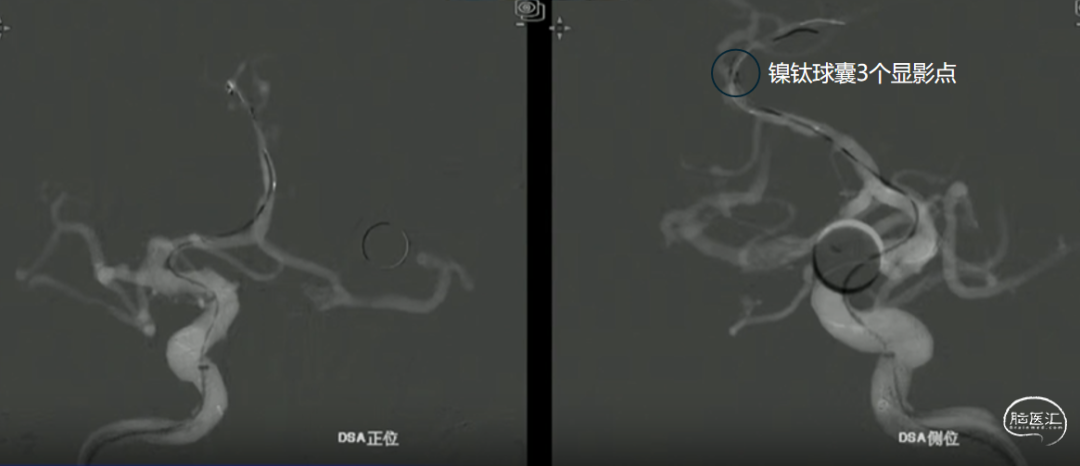

如意输送到位

心玮“如意”FDD-250-20mm 血流导向密网支架输送到位。

如意远端释放

动脉瘤近端锐角弯曲,颅内支撑导管位置较低,且血管迂曲,无法提供很好的支撑和力的传导,故支架推送中阻力较大,需双手操作,给予支架推送杆一定张力。

如意中段释放

心玮“如意”血流导向密网支架相较于其他钴铬合金材质,密网支架略软,释放远端动脉瘤不会影响血管的走形。

中段释放后,造影,动脉瘤滞留明显,支架贴壁打开良好,支架位置合适。